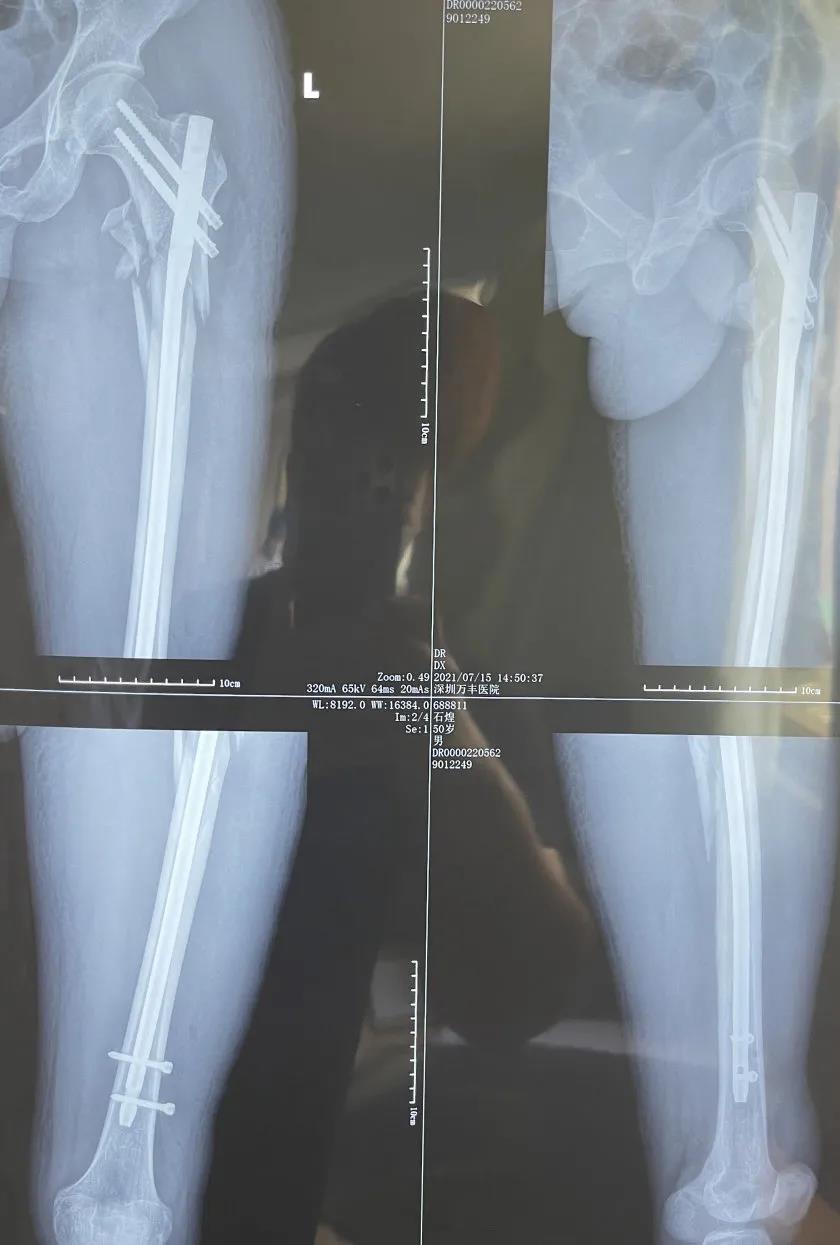

▲术后影像学资料

分三期手术,分别在全麻下行左股骨粗隆间粉碎性骨折及粗隆下骨折有限切开复位内固定术,左骼骨骨折合并骶骼关节分离切开复位内固定术,下颌骨粉碎性骨折切开复位内固定术(术后恢复了咬合关系,患者可以进半流质饮食),左尺骨鹰嘴粉碎性骨折切开复位内固定术,左跟骨粉碎性骨折切开复位活动术。手术均获得成功,病人骨折达到临床愈合,肢体功能恢复良好,无感觉障碍及并发症,伤口愈合良好。